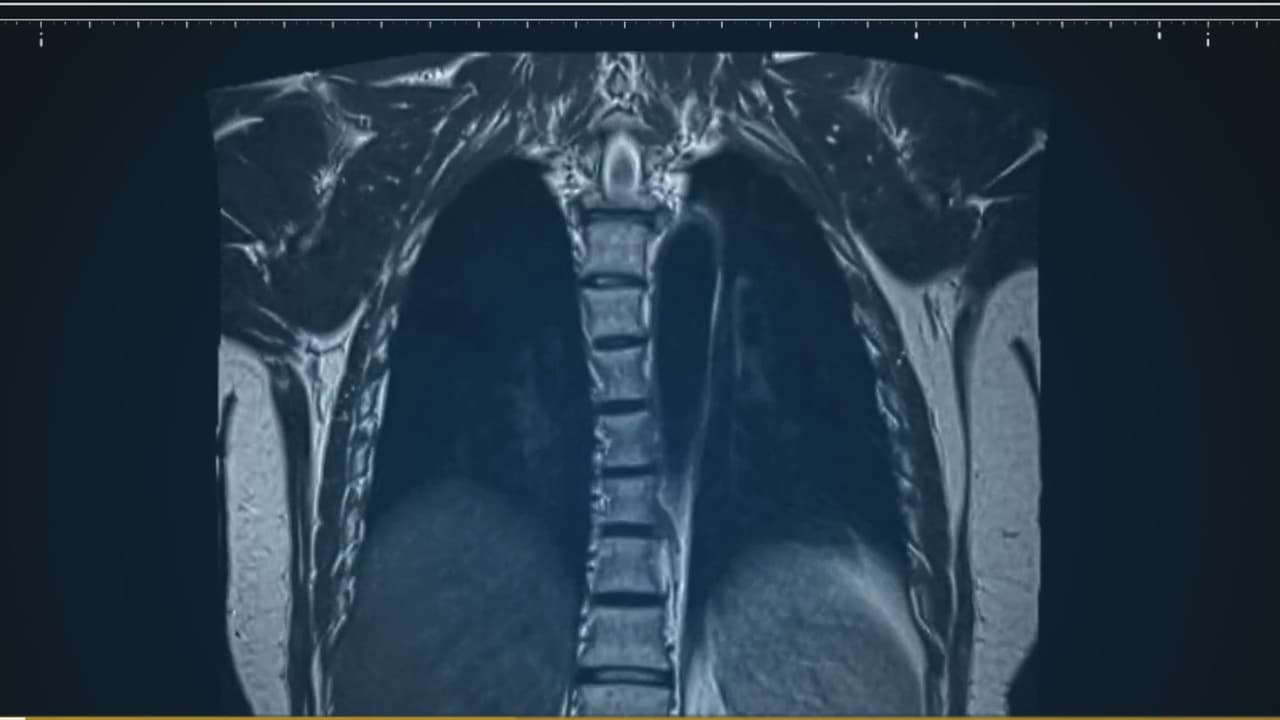

El cáncer de pulmón es una realidad que afecta a muchos. En este segmento, conversamos con el Dr. Eduardo Egea sobre los nódulos pulmonares, un signo temprano de esta enfermedad. Aprenderemos cómo detectar a tiempo estos nódulos, qué implica el diagnóstico y qué opciones de tratamiento existen.